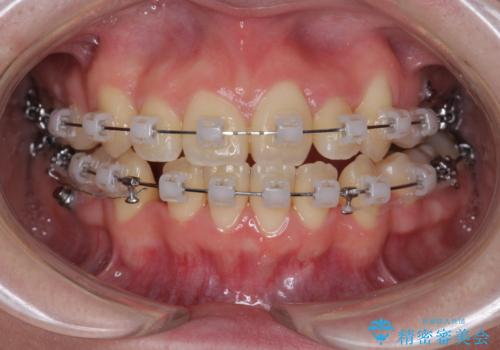

歯並びのせいで歯ブラシがしづらい マルチブラケットを用いた抜歯矯正

- 歯並びのがたつきにより歯ブラシがしづらく、今後虫歯になってしまう不安から、矯正治療を希望されて来院されました。

歯を並べるにはスペースが不足しているため、小臼歯の抜歯を4本行うマルチブラケット矯正による治療を計画します。

治療後は非常に歯ブラシがしやすくなったと、治療結果に満足いただくことができました。